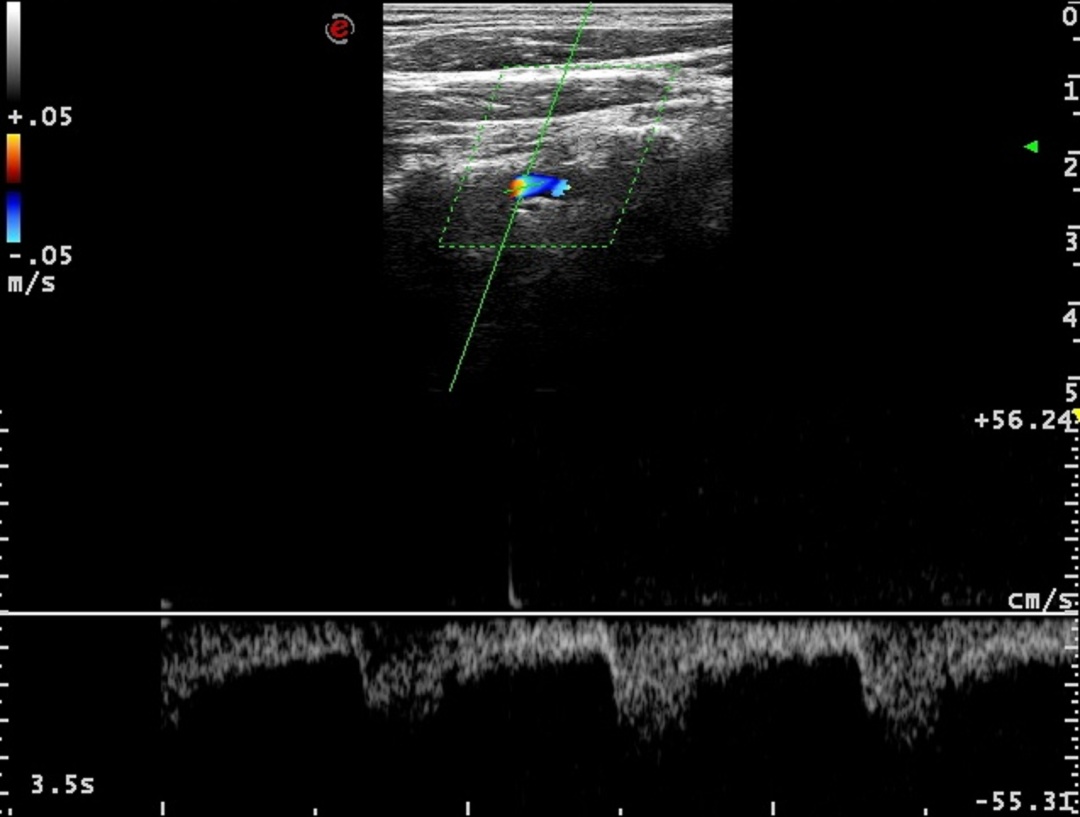

进一步超声评估显示,李伯伯右侧椎动脉血流频谱在收缩期和舒张期均呈完全反向,确诊为III型完全型窃血。基于这一明确诊断,心血管团队为其实施了锁骨下动脉支架植入术。术后,李伯伯的头晕及上肢无力症状完全消失,血压恢复对称,桡动脉搏动明显增强。医生特别叮嘱他控制运动强度,避免长时间上肢用力,并定期复查血管状况。

锁骨下动脉窃血综合征是一种因动脉狭窄或闭塞导致血流逆流的血管疾病,常见症状包括眩晕、耳鸣、患肢发冷疼痛等,严重时可引发脑梗死。瑞金医院专家指出,彩色多普勒超声是诊断该病的首选方法,可精准定位病变部位、评估狭窄程度,并为后续治疗提供依据。